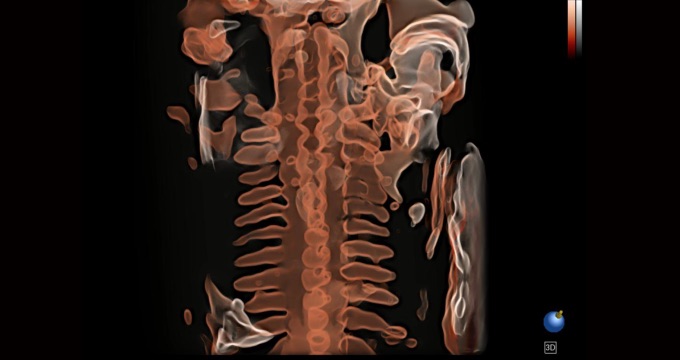

三維光影成像技術(shù)采用新型的渲染方式,增強(qiáng)邊緣信息,使得輪顯示清晰完整,為臨床提供豐富、直觀的三維結(jié)構(gòu),提供臨床診斷準(zhǔn)確性。